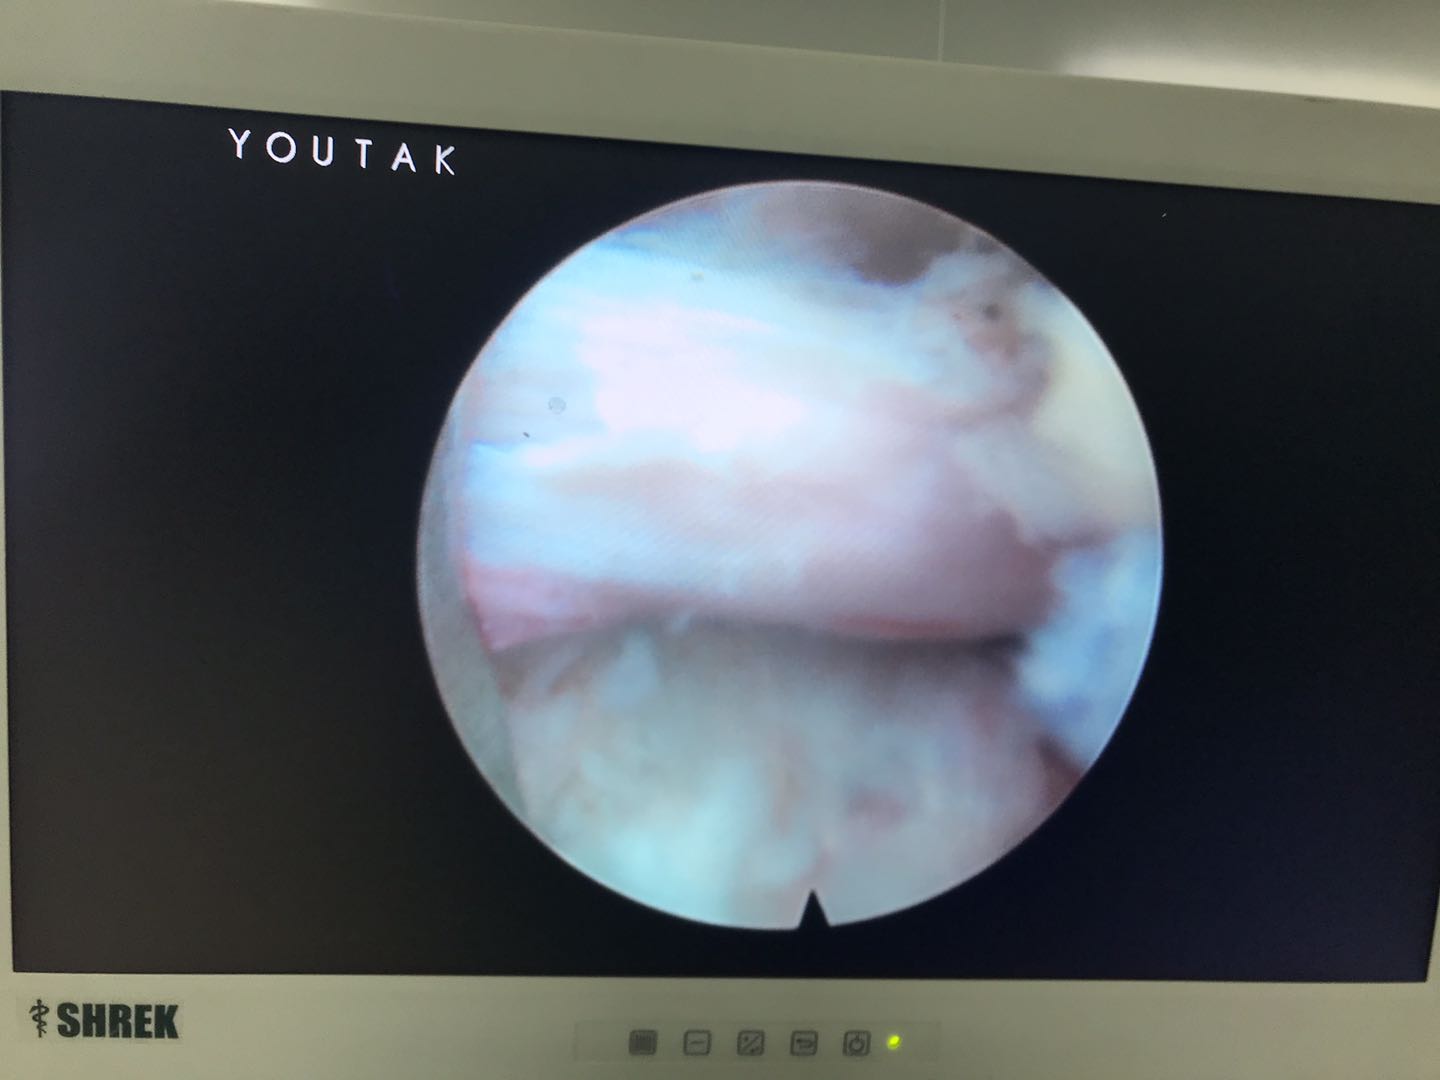

经过1小时的努力,胜利完成了手术!老奶奶的腰痛得到缓解!进行直腿抬高试验70阴性,加强试验阴性!